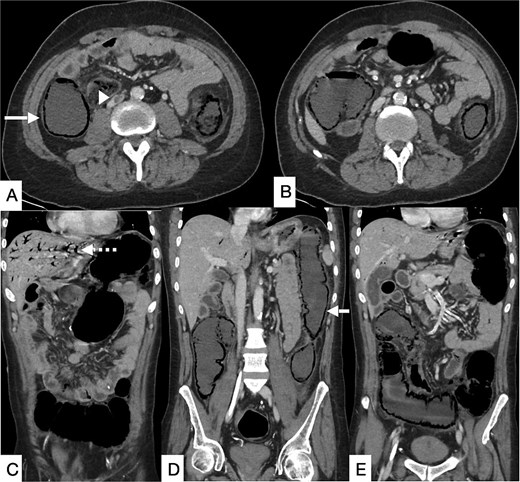

Contrast-enhanced computed tomography (CT) of the abdomen demonstrated long-segment ischemia extending from the transverse to descending colon, characterized by wall thickening, mucosal hypoenhancement, and pericolic fat stranding. A non-occlusive thrombus was noted in the IVC (Fig. 1). Review of prior CT angiography, performed several months earlier for gastrointestinal bleeding, had shown features of colonic angiodysplasia, including mucosal hyperenhancement, early venous filling, and serpiginous submucosal vessels (Fig. 2).

Contrast-enhanced CT of the abdomen and pelvis in axial (A, B) and coronal (C–E) planes showing a long segment of pneumatosis intestinalis involving the remaining descending colon, transverse colon, and proximal sigmoid colon, with suspicion of bowel perforation (bold arrow). Pneumobilia is present (dashed arrow). An eccentric intraluminal hypodensity within the IVC (arrowhead) is consistent with a non-occlusive thrombus, with a possible thrombus in the inferior mesenteric vein.